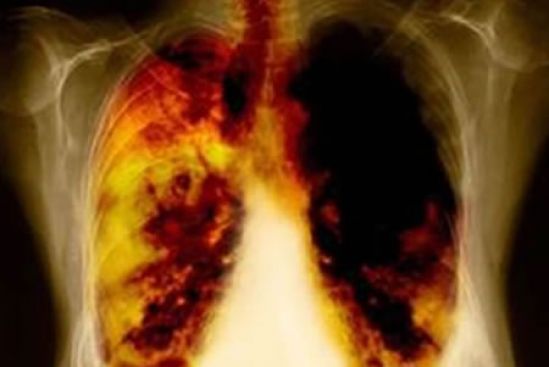

El 80% de los casos reciben un diagnóstico en etapas avanzadas, cuando el cáncer ya ha hecho metástasis y la tasa de supervivencia es del 4%. Esto se debe a que no se presentan síntomas hasta que la enfermedad se ha propagado. “El cáncer de pulmón es un tema que cobra gran relevancia al ser el más común en México y en el mundo y provocar más muertes, incluso por encima del cáncer de mama, colorrectal y próstata combinados”; aseguró el Dr. Jorge Arturo Alatorre, médico oncólogo del Instituto Nacional de Enfermedades Respiratorias Ismael Cosío Villegas (INER).

De acuerdo con el Dr. Alatorre, la mayoría de los cánceres de pulmón no causan ningún síntoma, sin embargo mencionó que entre los más frecuentes se encuentran la tos que no desaparece o que empeora, dolor en el pecho que a menudo empeora cuando se respira profundamente, tose o se ríe, ronquera, pérdida de peso y pérdida de apetito, tos con sangre o esputo (saliva o flema) del color del metal oxidado, dificultad respiratoria, cansancio o debilidad, infecciones como bronquitis y neumonía que no desaparecen o que siguen recurriendo y silbido de pecho.